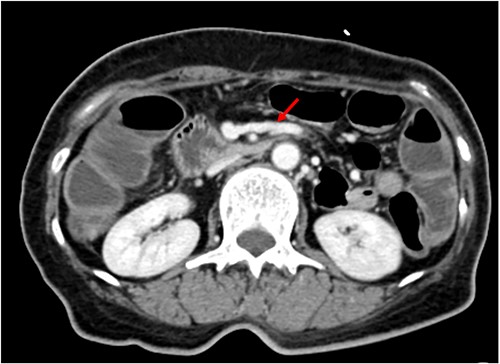

She underwent computed tomography (CT), which showed focal wall thickening at the transverse colon with direct invasion to the rectus muscle and subcutaneous fat layer of the anterior abdominal wall (Fig. 2). The surrounding multiple small lymph nodes were suspected of metastasis. There was another 2-cm tumor lesion in the sigmoid colon. She was diagnosed locally advanced transverse colon cancer and early sigmoid colon cancer after colonoscopy and biopsy.

Coronal (A) and axial (B) computed tomography image of abdomen and pelvis showing transverse colon cancer with direct invasion to the rectus muscle and suspicious invasion of superior mesenteric invasion.

Dilated jejunal first branch of superior mesenteric vein (red arrow).